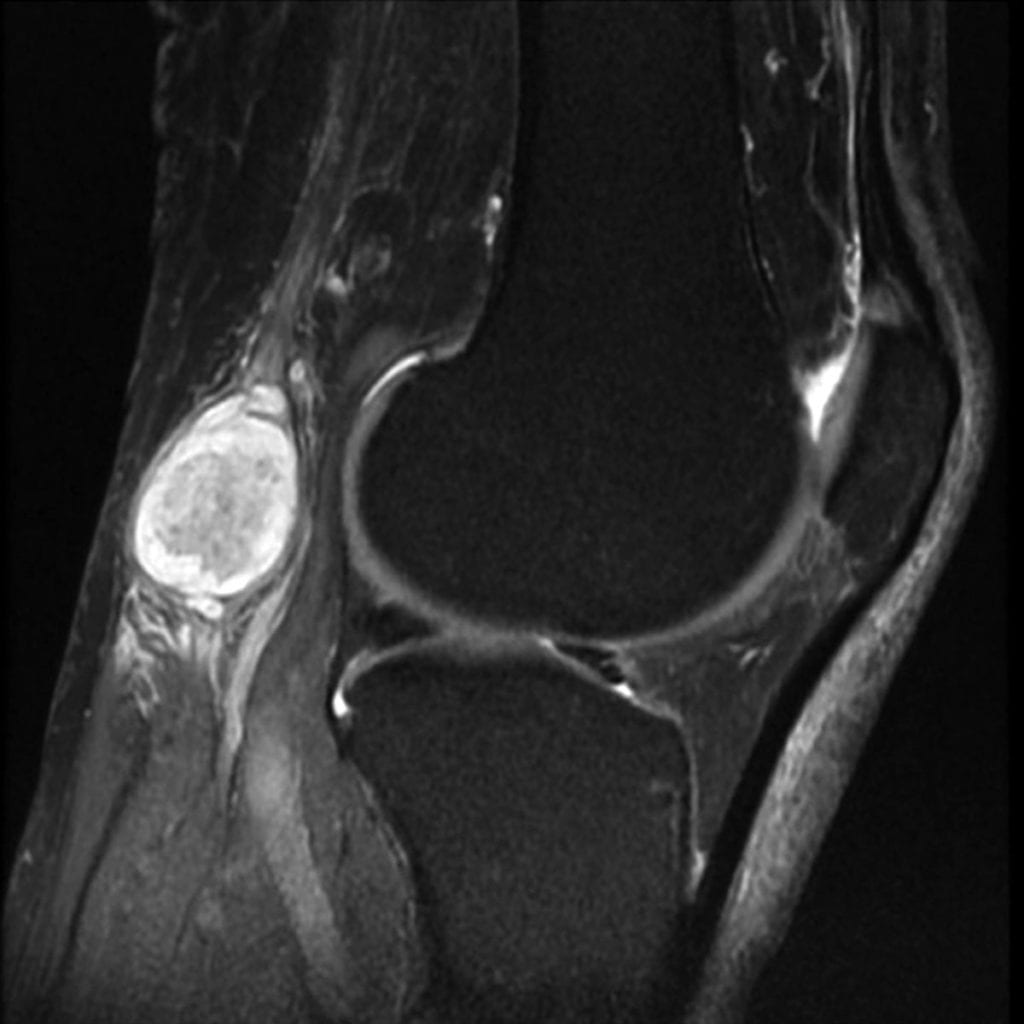

- МРТ;

В некоторых случаях они могут решить, что вам нужно пройти рентген или МРТ, чтобы они могли лучше рассмотреть кисту. Как только они смогут наблюдать это к своему удовольствию, они смогут диагностировать вас с кистой ганглия.

Для подтверждения диагноза выполняют рентгенографию, ультразвуковое обследование, компьютерную или магнитно-резонансную томографию.

Чтобы уточнить тип патологии, обязательно нужно сделать пункцию с биопсией для последующего гистологического изучения. Если более тяжелые заболевания исключены, а лабораторное исследование взятого биологического материала не обнаружило патологическое увеличение бактерий, то ставится диагноз «ганглиозная киста».